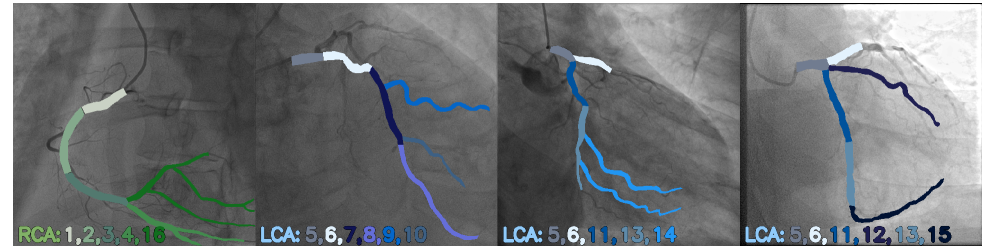

Figure 2: Example frames from angiography views with the coronary arteries highlighted. The coronary artery system consists of two main branches: the right (RCA, marked in green) and the left coronary artery (LCA, marked in blue). Based on the Syntax Score Methodology[8], RCA and LCA are divided into 16 segments. Segments 1, 2, 3, 4, and 16 correspond to the RCA, and the remaining belong to the LCA.